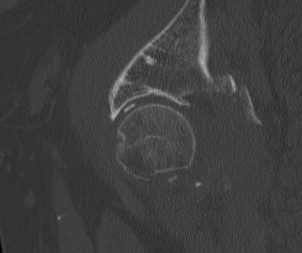

CT

- only with CT can < 2mm fragments be seen

3. Screen for retained fragments

Compulsory CT

- xray will not detect fragments < 2mm